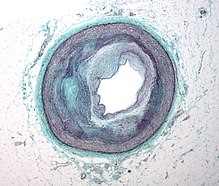

artery.crossectionPicture to the left is a  Micrograph of an artery that supplies the heart showing significant atherosclerosis and marked luminal narrowing. Tissue has been stained using Masson’s trichrome. As Dr. M. explained, old plaque is scar tissue, and may not necessarily cause such blockage. High performance on a stress test indicates no blockage of cornonary arteries. Unlike new plaque, old plaque does not flake off, risking heart attack or stroke, unlike new plaque. However, both contain calcium, so measures of plaque do not distinguish between the two. So, you can have a very high score for plaque, pass the stress test indicating no blockage, and have low risk. Yet most cardiologists don’t make such distinctions; they just prescribe statins. If my arteries looked like the one in the picture here, I could not have passed the stress test with ease, as I did.